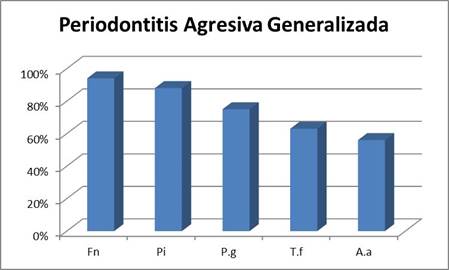

Periodontitis Agresiva Generalizada

Si bien en ambos tipos de cuadros F. nucleatum fue un microorganismo de alta prevalencia, se destacó fundamentalmente en los cuadros agresivos generalizados presentándose en casi el 95% de los pacientes.

En los cuadros generalizados, el microorganismo que le siguió en prevalencia fue P. intermedia (en el entorno del 90%), seguido por P. gingivalis en el 75% de las muestras y por T. forsythia en un 63%. Por otra parte, A. actinomycetemcomitans si bien es recuperado en varios pacientes, fue de los microorganismos estudiados, el menos prevalente presentándose en un 56% (Graf. 2).